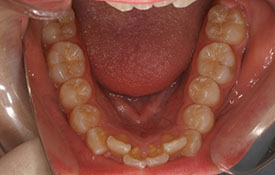

インビザラインの治療例:CASE-2

| プロフィール | 15歳 男性 |

| 所見 | アメリカから転院されて来られた方です。 インビザラインで上下顎の矯正治療を開始し下顎はアメリカで終了しており、上顎のみ治療の後期を担当しました。 アイライナーの装着は、1日平均22時間ほどでした。 |